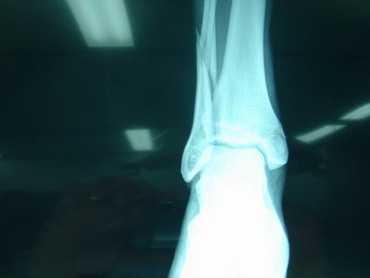

13 -5 -07 Durante el tercio de banderillas, de la lidia del 5º toro, ingresó en esta enfermería y fue asistido D. Pablo Hermoso de Mendoza de las lesiones que a continuación se especifican: Posible fractura 1/3 distal miembro inferior izquierdo con posibles afectación de tibia y peroné. Constantes normales. Miembro inestable, no dolor excesivo, ni frialdad distal, riego sanguíneo distal conservado, se inmoviliza con férula neumática y se traslada bajo control médico a clínica Sagrado Corazón de Sevilla. Pronóstico grave. Dr. D. Raúl Morales Maruri. |

14 - 5 - 07 El torero se interviene hoy a la 12,30 horas en la Clínica Sagrado Corazón de Sevilla. Se confirma diagnóstico provisional hecho en la enfermería de la plaza de Osuna. Fractura de tibia y peroné. Con las siguientes connotaciones: La fractura de peroné es completa y compleja consta de 4 fragmentos diferentes con desplazamiento de los mismos. es decir una fractura conminuta. La tibia presenta fractura maleolar con desplazamiento y además con respecto al tobillo existe una subluxación de la articulación debida a la rotura o explosión de la cápsula articular con desflecamiento de la misma. En resumen un cuadro complejo de tobillo inestable que precisa intervención quirúrgica inmediata. Se estabilizan las fracturas, se sutura la cápsula anterior, se reduce la subuxación, se administran factores de crecimiento y se inmoviliza extremidad. Pronóstico grave. Se estima un tiempo de recuperación de 90 días. Dr. Minguet. Dr. Periañez. Dr. Vaz. Dr. Morales |